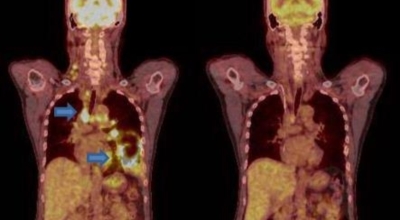

폐암 검사는 X-ray를 통해서 검사하는데 , 크기가 작거나 구석에 위치한 경우 확인이 어려운 경우도 있답니다. 그리고 조직 검사를 통해서 정확한 진단을 하게 돼요. 폐암이 발견되면 종양의 크기나 전이 여부 , 위치에 따라서 수술 여부를 결정하게 돼요.

악성 종양이 있는 폐의 일부를 절제하는 방법입니다. 초기에는 내시경 기구를 활용해 수술이 가능하기도 해요.

항암제를 이용한 치료 방법입니다. 폐암 4기 같은 경우에는 항암 화학요법이 유일한 치료방법이기도 해요. 폐암에 관해서 알아봤는데요.